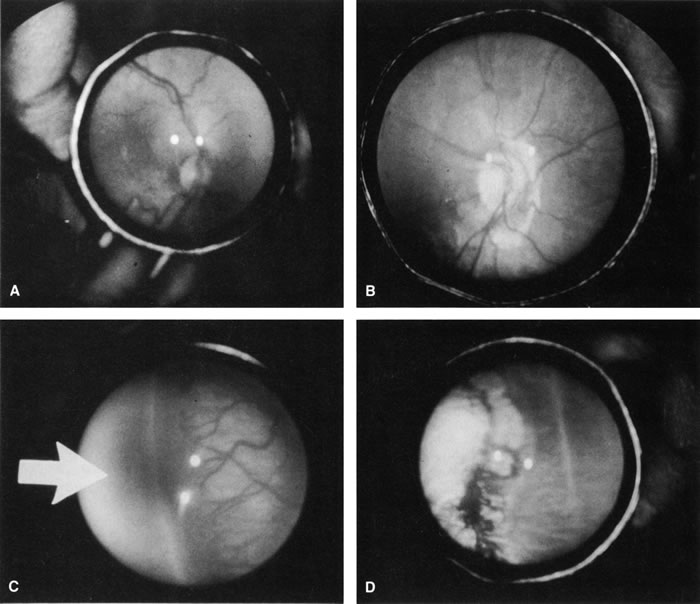

Several small prospective randomized trials have compared the efficacy of laser photocoagulation to cryotherapy for threshold ROP30,31,40,41 No statistically significant study has proven its efficacy, but they have suggested that laser treatment is as effective as cryotherapy in the treatment of threshold ROP (Fig. 6). A number of other studies have assessed the structural and functional outcomes following both argon and laser treatment of threshold ROP, with good results (Table 4).

Fig. 6. A. Peripheral neovascularization in zone I. B. Peripheral retina immediately after argon laser photo-coagulation. C. Peripheral retina 1 week after argon laser photocoagulation. D. Peripheral retina 1 month after argon laser photocoagulation. Note the complete regression of neovascularization.